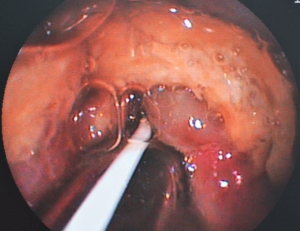

下の写真が当日、緊急の内視鏡検査を行った胸部食道の異物です。異物は胃の入り口の噴門部を越えることができず、噴門部の手前で引っかかっています。

”リンゴを飲み込んだ”、という飼い主さんの情報から、この塊が消化可能なものという判断して、内視鏡で胃内へ異物を落として終了いたしました。

次の写真が当日、緊急で行った内視鏡検査の様子です。唾液や分泌物を吸い込んで膨張した「牛皮ガム」が噴門部手前の胸部食道の出口で食道閉塞を起こしておりました。この部位は【ケース1】と同様に胸部食道で最も閉塞を起こしやすい場所です。

消化可能な異物ですから、内視鏡によって胃内へ落とすことを試みましたが、異物は角張って食道粘膜に食い込んでおり、さらに唾液等でベタベタになった牛皮ガムが食道粘膜と密着して胃に落とすことはおろか動かすことさえできませんでした。

最終的に周囲に潤滑剤を注入し、異物を粘膜から浮かせてようやく胃内へ落とすことができました。

下の写真をご覧になってみてください。この写真は食道の下流域、胸部食道から胃の入り口である噴門部(中央部のすぼまっているところ)を見ている内視鏡の画像です。

実はこの写真は胸部食道に詰まった異物を摘出した後のものです。異物は「牛皮のガム」でした。この写真は閉塞が起きてから、半日程度経過したところで内視鏡検査を行ったものです。

この画像は食道が圧迫に対していかに弱い臓器なのかを示す画像としてご覧ください。

下の写真で黄色矢印の先がへこんで周囲の粘膜が出血しています、中央部は「牛皮の尖った部分」に圧迫されて潰瘍を作っており、食道穿孔の危険性がありました。

また、緑矢印の先に広い範囲で赤黒く粘膜面の変色が見られます、こちらも圧迫によって粘膜面にうっ血が生じており、食道粘膜にダメージを起こしているのが分かります。